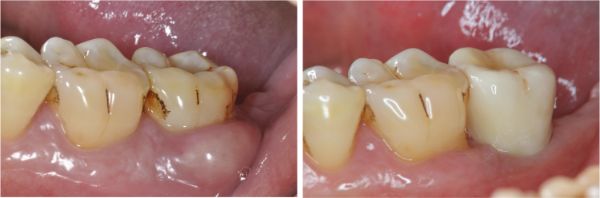

固位後口內照

術前、術後比較

使用單顆植牙,不需修磨正常的牙齒,清潔更方便,且咬合更強。